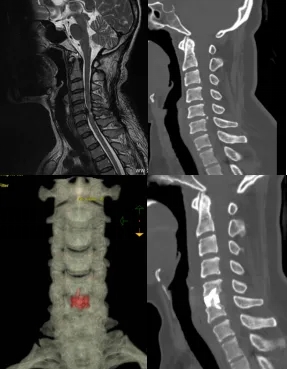

王先生六年来反复出现颈部疼痛,近期症状加剧甚至影响到正常行走。“有刺痛的感觉,走路像踩棉花一样,摔了好几次,一度怀疑中风了。”经详细检查,他被确诊为“脊髓型颈椎病”,颈5/6椎间盘严重突出压迫神经,如不及时治疗,可能导致四肢进行性瘫痪。

经海南医科大学第一附属医院脊柱外科黄涛主任团队评估后决定采用创新性的LUSE软镜下ACDF手术,以最大限度减压脊髓、恢复神经功能,同时降低手术创伤和并发症风险。

术中,黄涛主任团队通过软镜直视实现了对颈椎间盘病变的精准清除和脊髓减压,并在可视化引导下安全植入融合器,重建颈椎稳定性。患者术后恢复顺利,四肢肌力较术前明显改善,麻木症状逐步缓解,在随访过程中患者恢复良好,已能下床活动。